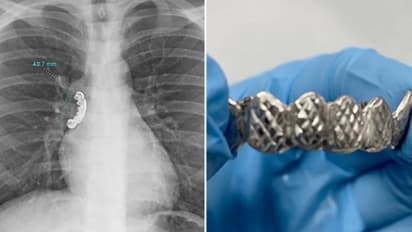

മരണം വരെ സംഭവിക്കാന് സാധ്യത ഉണ്ടായിരുന്ന ഇയാളെ ഉടൻ തന്നെ ആശുപത്രിയിൽ എത്തിച്ചു. തുടര്ന്ന് ഇയാളുടെ എക്സ്-റേ പരിശോധിച്ചപ്പോഴാണ് ശ്വാസകോശത്തിന്റെ ശ്വാസനാളത്തിൽ 4.1 സെന്റീമീറ്റർ ദീളമുള്ള വെപ്പു പല്ല് കുടുങ്ങിയതായി ഡോക്ടര്മാര് കണ്ടെത്തിയത്. ക്യൂറസ് മെഡിക്കൽ ജേണലിൽ ആണ് ഈ സംഭവത്തിന്റെ കേസ് സ്റ്റഡി പ്രസിദ്ധീകരിച്ചത്.

പരിശോധനകൾക്ക് ശേഷം, കുടുങ്ങിയ വസ്തു നീക്കം ചെയ്യുന്നതിനായി ഡോക്ടർമാർ ഇയാളെ ബ്രോങ്കോസ്കോപ്പിക്ക് വിധേയമാക്കി. കനംകുറഞ്ഞ ട്യൂബ് ശ്വാസനാളത്തിലൂടെ പ്രവേശിപ്പിച്ചാണ് ഈ ശസ്ത്രക്രിയ ചെയ്തത്. ശസ്ത്രക്രിയ വിജയകരമായി നടന്നും എന്നും റിപ്പോര്ട്ടില് പറയുന്നു.